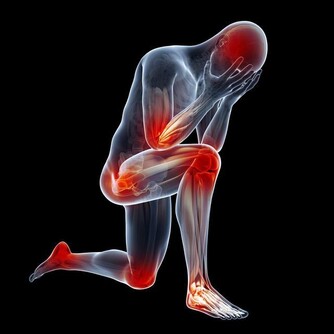

胃:怕冷 胃、十二指腸潰瘍發病有季節性,秋冬和冬春交替都是高發期,寒冷的天氣尤其要注意養胃。胃痛、腹部不適,消化能力降低,這時進食生冷食物就會引起或加重胃部不舒服的症狀。 心:怕咸 食鹽過度會給身體帶來高血壓、心血管疾病等隱患。鹽中含有大量的鈉離子,鈉會引起體內血容量的增加,所以食用過多的鹽,就會導致血壓升高,心臟負擔也會加重。 肺:怕煙 除了吸煙、被動吸煙外,廚房油煙、裝修污染等室內環境污染,也是引發肺癌的危險因素。研究表明,廚房通風不良相比通風良好者,患肺癌風險增加了49%。 腎:怕肉

經常大魚大肉,容易導致蛋白質攝入超標,長期如此會增加腎臟負擔。腎臟不好的患者,如果繼續多吃肉,更會加重對腎臟的損害。 肝:怕胖 脂肪肝與“節儉基因”有關,一個人體重增加了3%~5%,就很有可能從原先沒有脂肪肝變成患有脂肪肝。 一般而言,肥胖的過程是先胖到肝,再胖到腰,最後是整體的體重超標,成為一個名副其實的胖子。因此,明顯的胖子患脂肪肝比較容易理解。 當然,臨床上發現瘦人也有脂肪肝。這是因為胖不胖,不能單憑體重指數,還要看體脂比,如果肌肉少,脂肪多,還是有可能患脂肪肝。 腸:怕坐 研究發現,喜歡久坐不動的男性,其結腸息肉復發的風險會增高。而任由這種良性腫瘤發展的結果是:可能會引起結腸癌。 而且,已被診斷患有結腸直腸癌的患者,如果每天長時間坐著,死亡的風險就會增加;如果讓身體保持運動狀態,生存希望就會增加。 胰:怕撐 若飲食不當,容易誘發胰腺炎發作。如暴飲暴食、過度飲酒,都容易對胰腺造成刺激,引發急性胰腺炎。 部分患者一發病就十分凶險,若搶救不及時,很容易導致死亡。 膽:怕甜